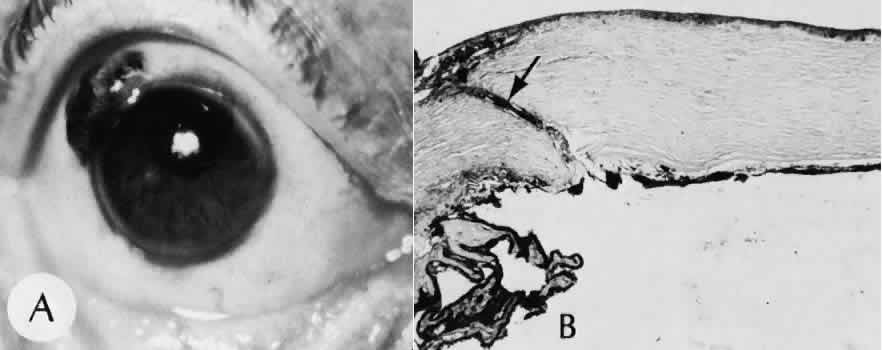

Epithelial downgrowth (ingrowth) (Fig. 44) is one of the most serious causes of pseudophakic glaucoma, in which surface epithelium (probably from the conjunctiva) grows into the anterior chamber. This condition is more likely to occur with fornix-based conjunctival flaps than with limbus-based flaps and in eyes with problems in wound closure, such as vitreous loss, wound incarceration of tissue, delayed reformation of the anterior chamber, or frank rupture of the limbal incision, and when instruments such as iridectomy forceps are contaminated with surface epithelium before they are introduced into the eye. Epithelial downgrowth causes an anterior chamber angle closure by means of peripheral anterior synechiae or lines an open anterior chamber angle and obstructs aqueous outflow mechanically. Histologically, the epithelium is seen to grow most luxuriously and in multiple layers on the iris where there is a good blood supply, but it tends to grow sparsely and in a single layer on the posterior surface of the avascular cornea. The epithelium may extend behind the iris, over the ciliary body, and even far into the interior of the eye.

Fig. 44. A case of epithelial downgrowth. A. The clinical findings are subtle and consist of a translucentmembrane on the posterior corneal surface, often contiguous with an ocular wound, characterized by a well-defined, linear leading edge. In this case, the leading edge is just above the corneal light reflex. B. In contrast, in this case, the leading edge is just below the corneal light reflex. The surgical procedure in both cases appears to have been complicated because of the presence of sector iridectomies. C. In this case, surface stratified squamous epithelium lines the posterior cornea (including the posterior aspect of the clear corneal wound) and extends over delicate trabecular tissue onto the anterior surface of the iris. The epithelium will adapt the tissue over which it grows to produce an adhesive surface appropriate to its attachment requirements. This adaptive process that is an advantage for the epithelium will permanently destroy the function of the trabecular meshwork over which the surface epithelium extends. D. The actual site of the fistula allowing the epithelium to gain access to the internal surfaces of the eye is rarely found on histologic sections. Higher magnification of the area of the wound, however, does show the presence of foreign material in the incision. Polarized material (inset) consistent with degenerating silk suture is present. Invasion of the epithelium along a suture tract is one possible route of entrance. (Hematoxylin-eosin stain with and without polarization; A, × 21; B, × 101)

Iris cyst formation (Figs. 45 and 46 is also caused by implantation of surface epithelium onto the iris at the time of surgery or trauma. The cyst generally grows slowly and is accompanied by peripheral anterior synechiae. If extensive, the cysts may cause a secondary chronic closed-angle glaucoma. Histologically, the cyst is lined by stratified squamous or columnar epithelium, sometimes containing mucous cells, and is filled with keratin debris (white or pearly cysts) or mucous fluid (clear cysts).

Fig. 45. Two cases of epithelial iris cyst formation following cataract extraction. A. Instead of forming a flat sheet to cover the posterior cornea and the anterior iris, the invading epithelium has formed a cyst in the anterior chamber. The cyst usually retains some continuity with the original wound but also may become free-floating in the anterior chamber. B. In this case, there is extensive distortion of the iris. The type of ingrowth, sheet or cystic, is a major determinant of the method of treatment used. C. The histologic character of the cyst lining indicates the presence of goblet cells. The origin of these cells may have been from the conjunctiva. In this rare circumstance, the cyst may become filled with mucous. (Hematoxylin-eosin stain; × 101.)